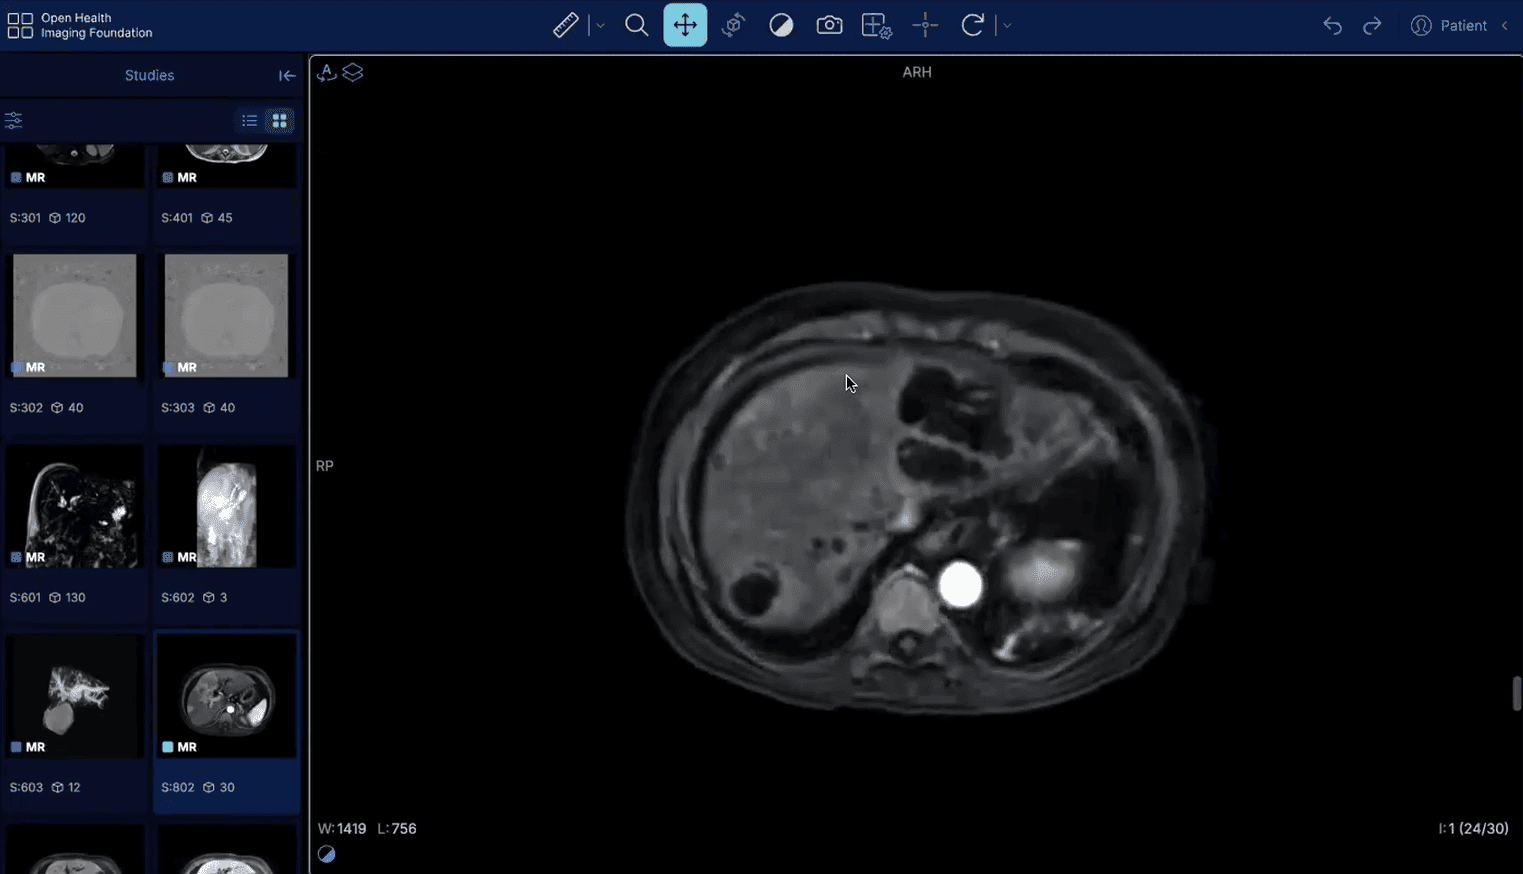

Acesse um PACS com exames reais selecionados para treinar raciocínio diagnóstico como na rotina de um grande serviço de referência.